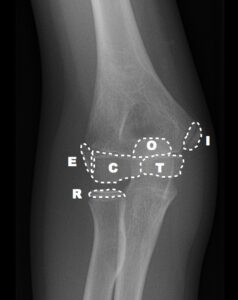

Bu noktaların ortaya çıkma zamanı tahmin edilebilir ancak hastadan hastaya, yaşa, cinsiyete, gelişime göre farklılık gösterebileceği unutulmamalıdır. Karşı taraftaki dirsekle karşılaştırılması patolojik görünüm ya da yapısal farklılığın ayırt edilmesinde yardımcı olur. Bu kemikleşme merkezlerinden ilk ortaya çıkanı Kapitulumdur. Ortaya çıkma sırasına göre “CRITOE” kısaltması kullanılabilir. Kapitulum hariç bu merkezler kızlarda erkeklere göre daha erken görülmektedir.

| KIZ | ERKEK | YAKLAŞIK | |

| C – CAPİTULUM | 1 YAŞ | 1 YAŞ | 1 YAŞ |

| R -RADİUS | 4 YAŞ | 5 YAŞ | 3 YAŞ |

| I – INTERNAL(MEDİAL) EPİKONDİL | 5 YAŞ | 7 YAŞ | 5 YAŞ |

| T – TROCHLEA | 8 YAŞ | 9 YAŞ | 7 YAŞ |

| O – OLECRANON | 8 YAŞ | 10 YAŞ | 9 YAŞ |

| E – EKSTERNAL(LATERAL) EPİKONDİL | 11 YAŞ | 12 YAŞ | 11 YAŞ |

[box type=”info” align=”aligncenter” class=”” width=””]Basitçe ilk merkez olan Kapitulumun 1 yaş civarında ortaya çıktığını diğerlerinin ise yaklaşık 2’şer yıl arayla ortaya çıktığını söyleyebiliriz.[/box]